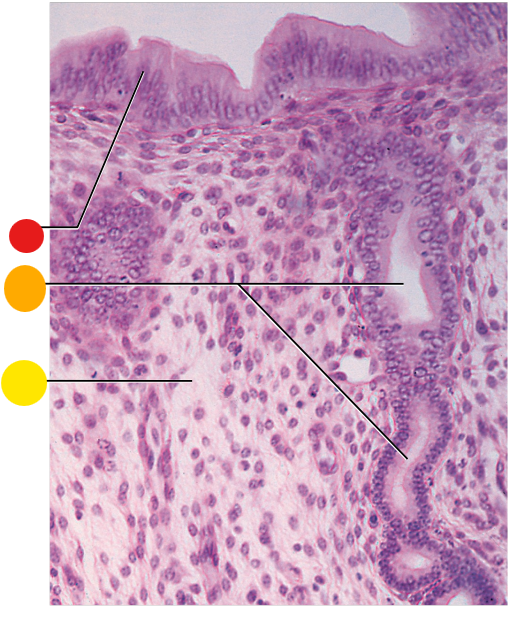

red

primordial follicles

red

primary follicles

red

tunica albuginea

orange

primary oocyte

yellow

primordial follicles